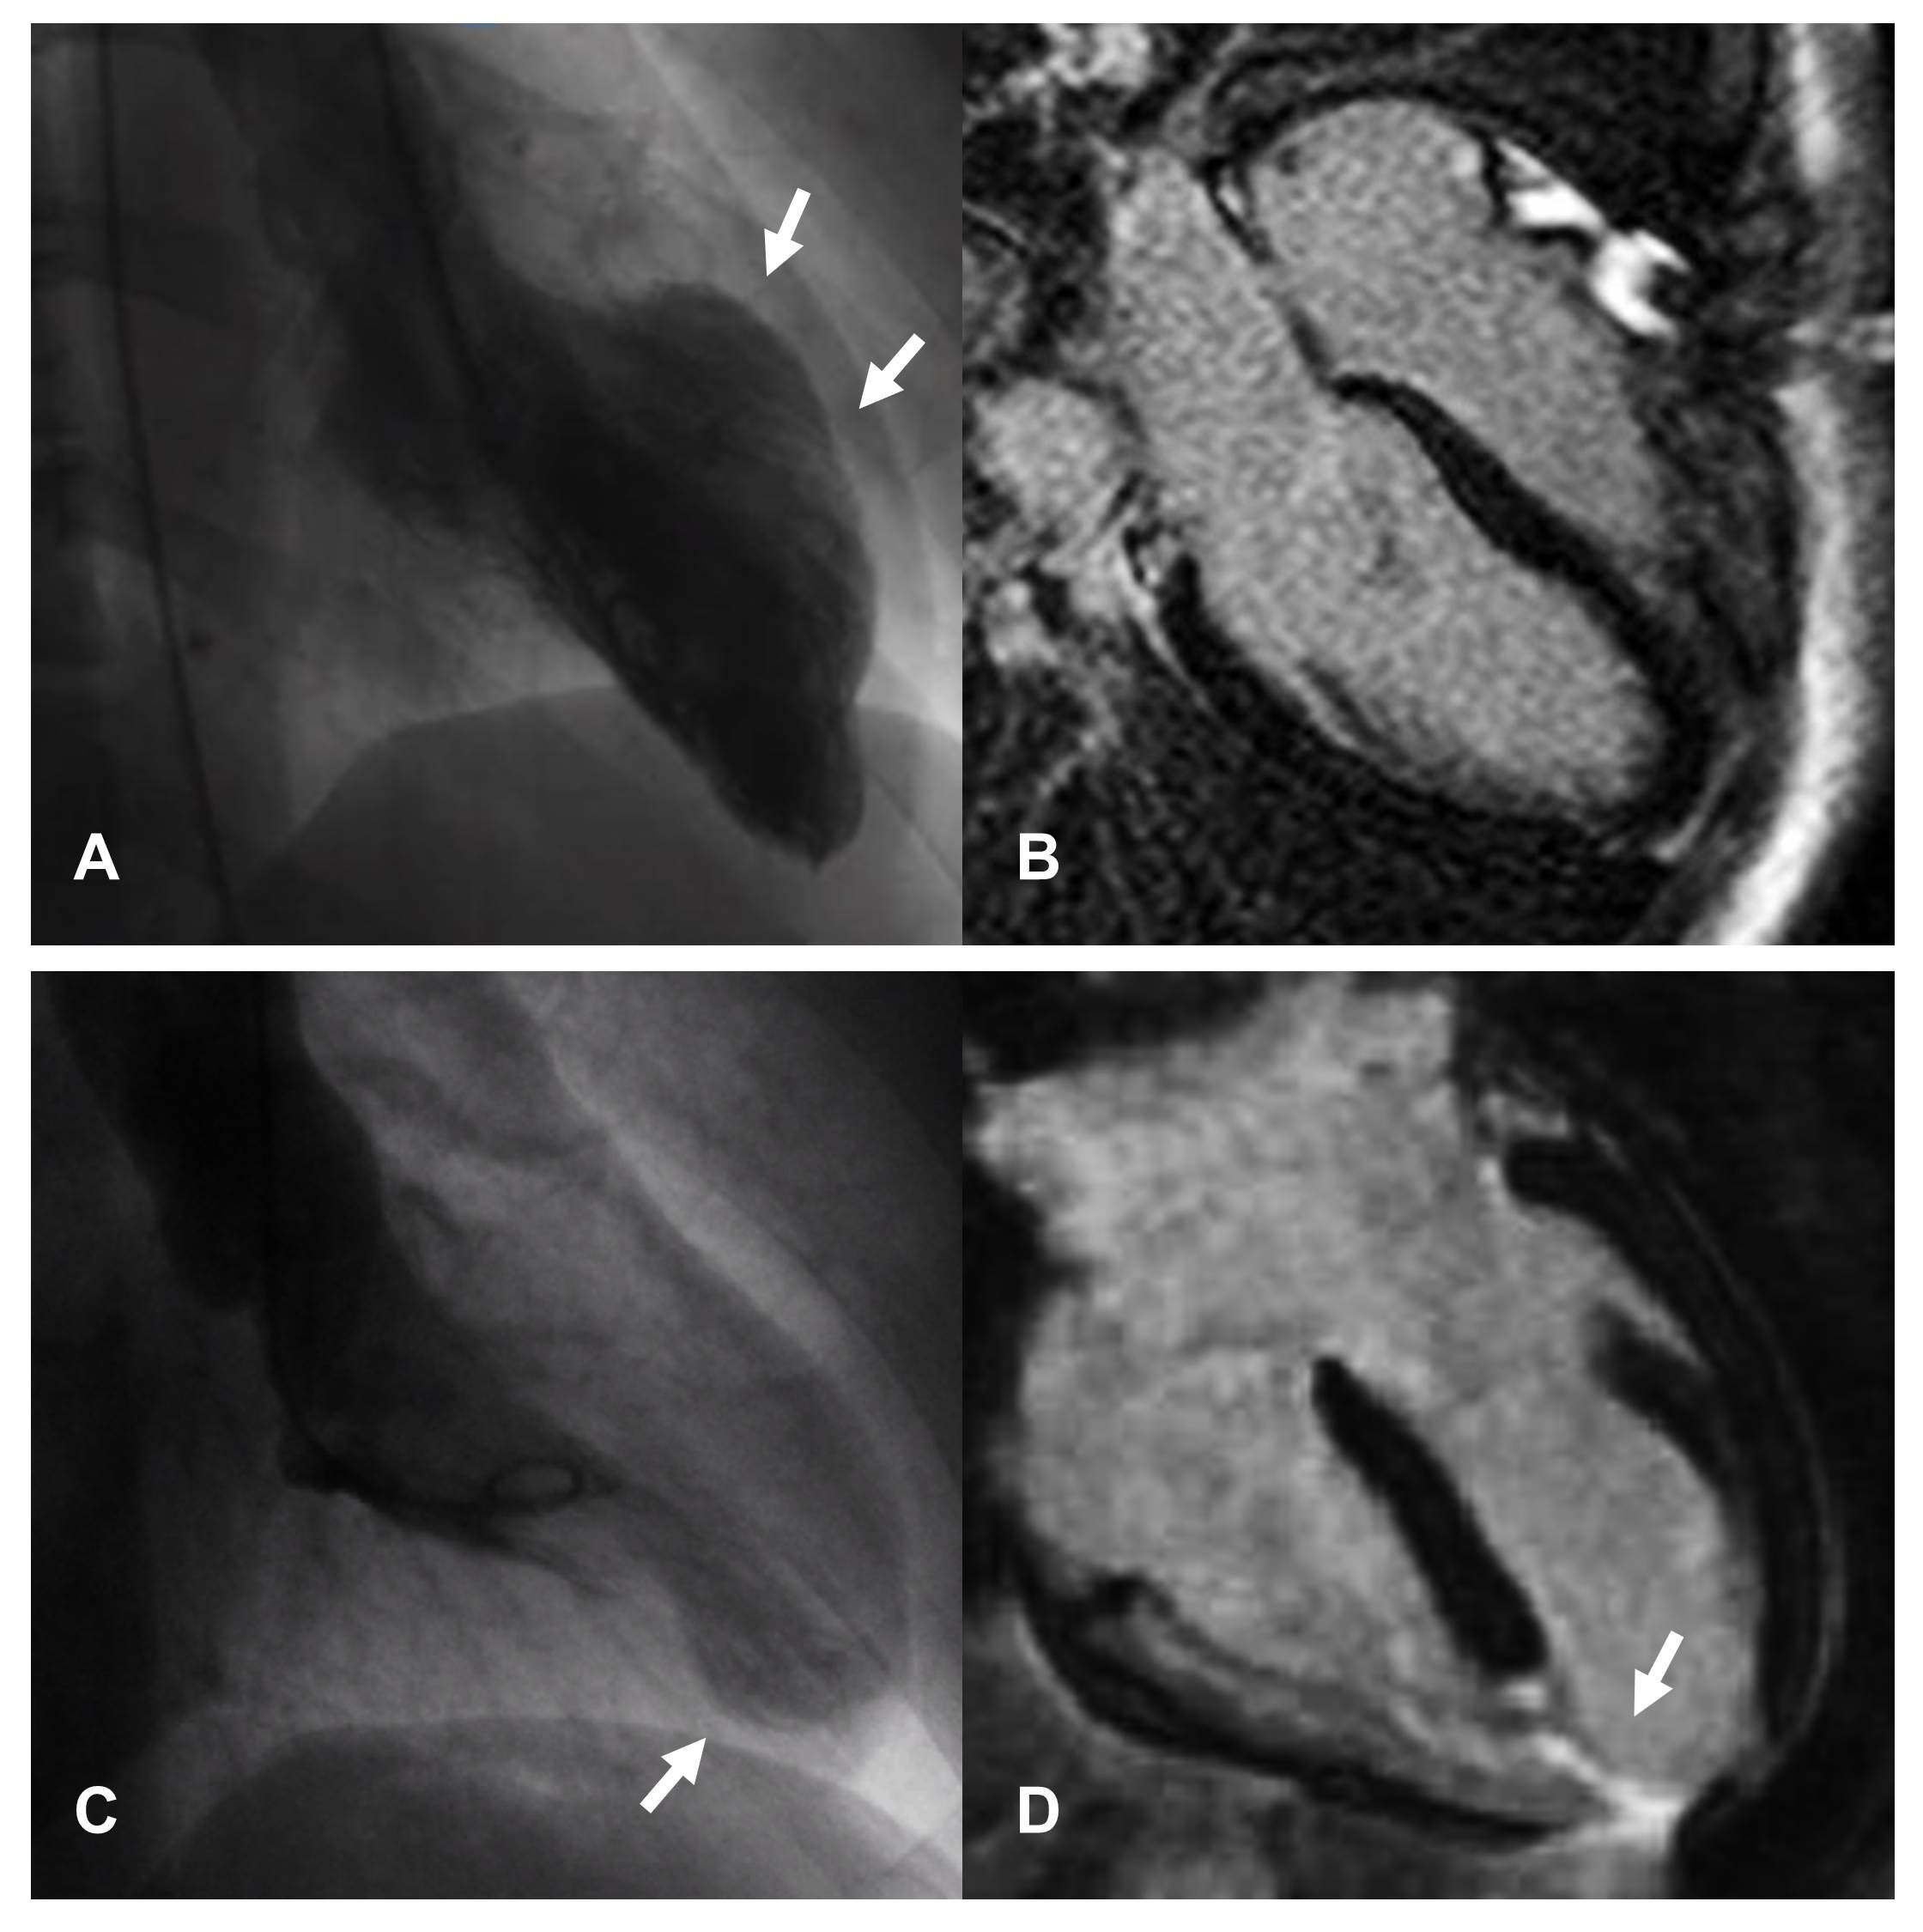

CMR is the gold standard non-invasive imaging tool in cardiovascular medicine for visualizing cardiovascular anatomy, quantifying chamber volumes and systolic function and characterize myocardial tissue [100]. Indeed it is able to identify and quantify non-vital areas, fibrosis and edema in the context of normal myocardium. Classic CMR appearance during the acute phase of TTS includes widespread myocardial edema, mostly distributed in the areas of contractile dysfunction [101], in the absence of significant replacement fibrosis at late gadolinium enhancement (LGE) imaging. However, presence of LGE areas has been reported [102], and linked to adverse outcomes [103]. Several bystander diseases associated with LGE areas might characterize patients with TTS, including previously unrelated myocarditis, AMI or known obstructive CAD [76, 104]. CMR should be performed in the acute phase, when available, in all TTS patients [22, 77] in order to differentiate TTS from other conditions with similar clinical presentation, such as myocardial infarction with non-obstructive coronary arteries (MINOCA) or myocarditis, and thus to guide the therapeutic decision-making process [105, 106, 107]. Additionally, performing early CMR would help identify typical complications of acute TTS, such as right ventricular involvement and ventricular thrombosis, which may be difficult to observe with TTE [108]. Unfortunately, CMR imaging cannot be always performed easily in the acute setting of TTS. The ESC position statement on TTS acknowledged this issue, suggesting to perform CMR preferentially for patients with dubious clinical presentation or suspected myocarditis [109]. CMR is also particularly useful in the subacute and chronic phase in order to evaluate residual edema and confirm the diagnosis, especially in case of less common presentations, such as in young, males or patients with atypical anatomical variants (midventricular [110], basal [111], and focal [112, 113] motion patterns) (Fig. 3, Ref. [72]). A low-grade myocardial edema may be still present at 3-month follow-up after the acute event, being linked to persistent symptoms as well as increased natriuretic peptide [114]. New advanced CMR techniques may provide an accurate and sensitive detection of edema and intramyocardial fibrosis and evaluation of myocardial chambers deformation (Feature-tracking CMR) similar to speckle-tracking echocardiography [115]. In particular, novel CMR mapping sequences allow a parametric quantification of interstitial expansion in the myocardium, with signal intensity mainly depending on extracellular water (T2 mapping) as well as fibrosis and infiltration (native T1 and extracellular volume mapping). Studies performed in the acute phase suggested concomitant increase of native T1 and T2 secondary to widespread edema [116, 117, 118]. High T2 values were related to lower acute LVEF [119] and delayed recovery along with native T1 [120]. At three months, persisting abnormalities can be detected [120, 121], while also in the long-term (more than one year after the acute event) native T1 has been described as persistently elevated [65] suggesting long lasting effect of the TTS event. However, native T1 is a very sensible imaging biomarker, influenced by a variety of factors including edema and, among others, previous chemotherapy [122], chronic kidney disease [123], arterial hyertension [124]. Hence, the presence of higher than normal native T1 values even before the TTS attack cannot be excluded in such a comorbid population. Fig. 4 shows CMR imaging findings of a TTS patient two weeks after the acute event.

Fig. 3.Images of two female patients hospitalized for chest pain arising after emotional stress. In both cases, coronary angiography documented the absence of significant coronary artery disease and ventriculography shows patterns attributable to atypical forms of TTS, with focal involvement of the middle segments of septum and anterior wall (A) and part of the apex (C). CMR performed in the first patient, shows absence of replacement fibrosis (B) confirming the diagnosis of TTS. In the second patient, CMR documents the presence of transmural necrosis, corresponding to the area of kinetic alteration and probable consequence of a vasospasm (D); therefore excluding the diagnosis of TTS. From L. Arcari; L. Cacciotti; L. R. Limite; M. Sclafani; I. Passaseo; G. Marazzi et al. Tako-Tsubo syndrome: long term prognosis and outpatient follow-up. Outpatient Cardiology. 2018; 4: 249–261 [72].